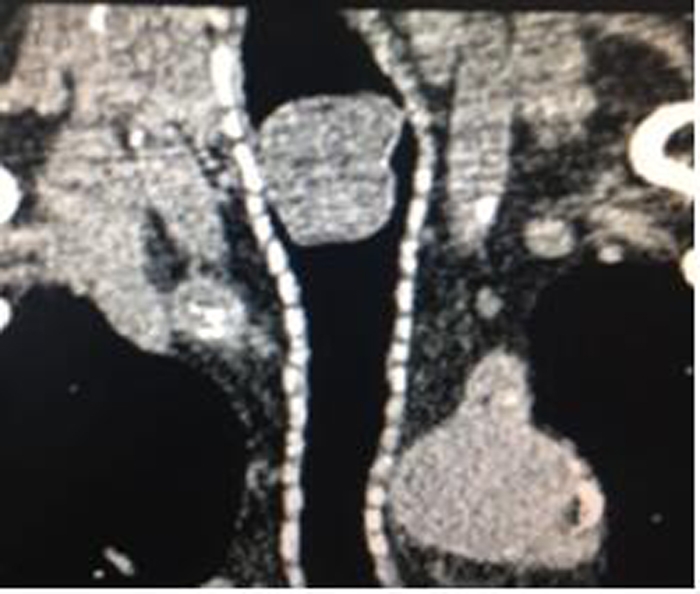

??? 通過CT檢查找到了病根——原來,讓他久咳不愈的罪魁禍?zhǔn)撞皇撬J(rèn)為的支氣管炎,而是一個(gè)腫瘤!該腫瘤直徑22毫米,已經(jīng)堵住了氣管上部,讓原本暢通無阻的氣管僅有一個(gè)縫隙的空間通氣。

CT影像圖

??? 潘先生“生命通道”被堵,隨時(shí)可能引起窒息,病情非常危重。直徑22毫米的腫瘤長在氣管里實(shí)屬少見,要想成功摘除它也不是件容易的事情。本著一切從病人出發(fā)的宗旨,必須要考慮如何能減輕病人的痛苦,降低就醫(yī)費(fèi)用。